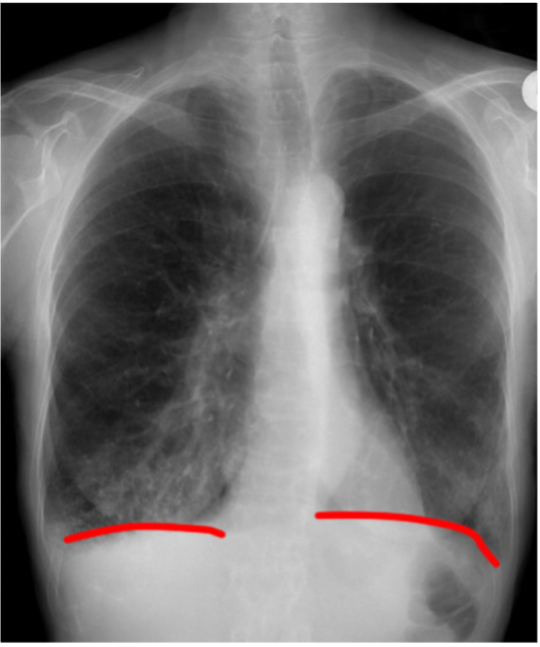

Q

How can you tell if a CXR has been taken during a good inspiration?

Count the anterior ribs on the right → 6 anterior ribs should be visible above the right hemidiaphragm

Anteriorly, which rib should intersect the diaphragm and where?

A

8

How can you assess for hyperexpansion on a CXR?

1. Count ribs → >7th anterior rib intersecting the diaphragm at the mid-clavicular line

2. Check for flattening of hemidiaphragms